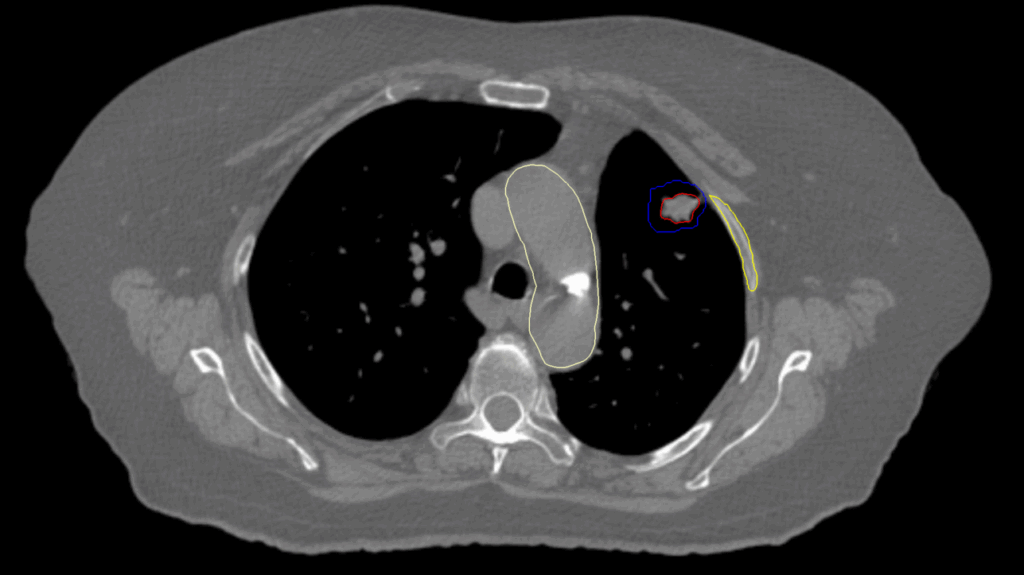

Planning CT Images

PTV(s) Volume

PTV, 5.17 cc